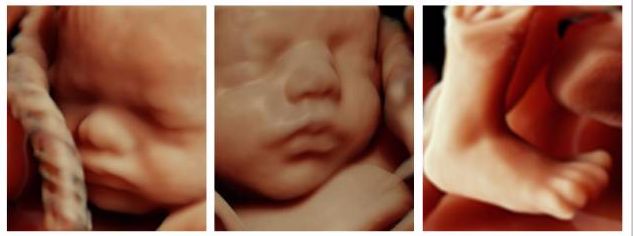

金标版GE-E10四维彩超是美国GE公司四维彩超的最新成员,专为尖端的妇女健康影像而设计,可广泛应用于妇产超声临床领域。尤其在产前超声筛查、孕早期成像、胎儿心脏成像、妇科泌尿和生殖医学等领域表现出色。

360°立体动态成像技术可清楚地显示子宫情况、输卵管形态、输卵管积水、通畅情况、伞端是否与周围组织粘连,大大提高输卵管的显示率和准确性;还能全方位立体动态地观察到胎儿生长发育状况。